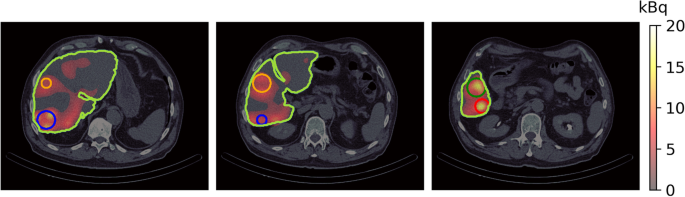

The SPECT/CT image obtained from Technetium \(^{99m}\)Tc albumin aggregated (\(^{99m}\)Tc-MAA) pretreatment simulation before \(^{90}\)Y hepatic radioembolization was used to calculate the absorbed dose by applying FLUKA MC and Voxel Kernel Convolution (VKC) [26]. Figure 1 shows three axial slices of the image of a patient who was administered \(185 \, MBq\) of \(^{99m}\)Tc-MAA. The image size was \(512 \times 512 \times 258\) pixels and a resolution of \(0.98 \times 0.98\times 0.98\,{\text {mm}}^3\). Also, images show the segmentation of the liver and 5 VOIs. Biodistribution of \(^{99m}\)Tc-MAA and \(^{90}\)Y microsphere was considered identical.

Figure 5 shows the absorbed dose map calculated by (A) MC and (B) VDK for the same three axial slices shown in Fig. 1, and (C) shows the gamma index for the criterion \(3\,\text {mm}/3\%\). The activity of each voxel was calculated by Eq. 14 and applied to Eq. 15. The voxelized kernel was calculated for each voxel where activity was greater than 0 using the calibration of Schneider et al. [56] to transform the Hu to the corresponding material compound. The sDPK for 90Y was calculated using Eq. 6 and the monoenergetic sDPK predicted by the RC model with Lasso as base regressor.

The mean absorbed dose calculated by MC for the liver and the five VOIs considered is greater than the mean absorbed dose calculated by VDK by approximately \(7\%\). The standard deviation means of absorbed dose at voxel levels calculated by FLUKA was less than \(9\%\) in the whole liver, and less than \(1\%\) in 5 VOIs considered. Table 5 summarizes the results obtained for the entire liver and the five VOIs.

In more than \(94\%\) of voxels, the gamma index was less than 1 for the \(3\,\text {mm}/3\%\) criterion in all regions considered. Figure 5C shows gamma index maps for the same three axial slices. As can be seen, at a zone of high dose the gamma index is greater than 1.